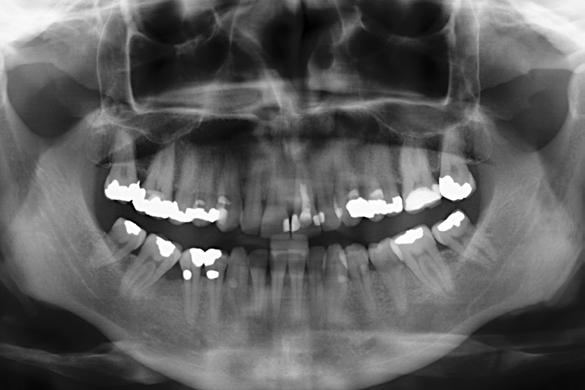

Figuras 1 y 2. Imágenes iniciales de la paciente. Se observa el diente en posición 21 con un cambio de color evidente y supuración espontánea a través del surco gingival. Asimismo, se aprecia el impacto estético del cambio cromático en la sonrisa y en el aspecto del frente anterosuperior.

Figura 3. Radiografía de la zona que muestra el tratamiento previo de apiconformación realizado en el incisivo para lograr el cierre apical, actualmente fracasado. Se observa además una lesión quística asociada al ápice.

Caso clínico

Se presenta el caso de una paciente femenina de 47 años de edad al inicio del tratamiento, quien acude a consulta por dolor y supuración en el incisivo central superior izquierdo. En las imágenes iniciales se observa un diente con un cambio de color llamativo y una supuración espontánea a través del surco gingival (Figura 1). Esta alteración cromática, además de reflejar un problema asociado al diente, afecta de manera significativa la estética del frente anterior, como se aprecia en la imagen de sonrisa (Figura 2).

El diente había sufrido un traumatismo durante la infancia de la paciente y, tras la pérdida de vitalidad pulpar,

Rehabilitación de incisivo central con implante diferido y sobrecorrección con injerto óseo particulado y PRGF-Endoret

se realizó un tratamiento de apiconformación que, al momento de la revisión, mostraba signos de fracaso, con evidencia de infección y clínica sugestiva de fractura radicular (Figura 3).

Estos hallazgos confirman el éxito del procedimiento quirúrgico y de la posterior carga progresiva, con un mantenimiento óptimo de los tejidos duros y blandos a lo largo de más de dos décadas (Figura 15). Los cambios entre el momento inicial y el final del tratamiento son evidentes, especialmente al comparar la imagen intraoral de la primera visita con la tomada a los 22 años, donde la mucosa que rodea al diente 21 —y posteriormente al implante— se muestra engrosada, en buen estado de salud y con una estética destacable. Asimismo, la comparación entre la radiografía inicial, que evidenciaba el fracaso del tratamiento de conductos del diente en posición 21, y la radiografía a los 22 años, que muestra el implante sin pérdidas óseas asociadas, resulta elocuente (Figuras 16 a 19).